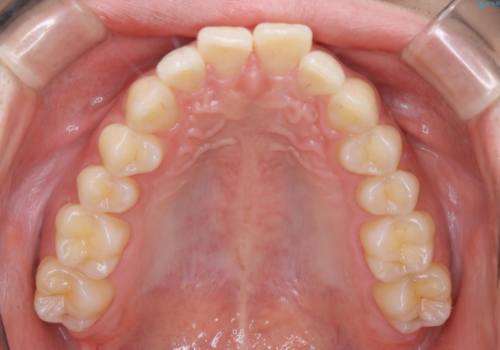

- 口元の突出感は気にならないが、上の前歯の角度と、下の前歯のがたつきが気になるとご相談にいらした方です。なるべく費用や治療期間を抑えて治療したいとのご希望に合わせて治療を計画しました。

この患者様への治療方針として、奥歯から少しずつ歯を移動させる方法と、歯をわずかに削って並べる方法とをご提案しました。短期間での治療を望まれたため、歯をサイズダウンさせて歯を並べました。わずかではあるものの、削った歯は元には戻せないことを十分ご説明し、ご理解ご了承を頂いた上で治療を行いました。